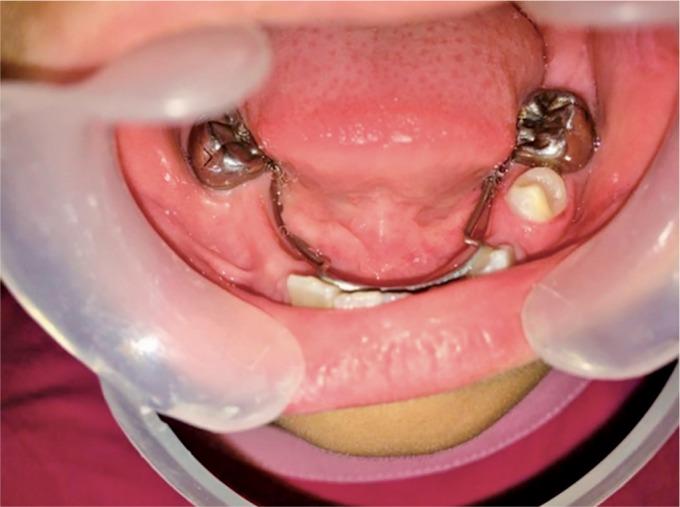

Dentinogenesis imperfect is a hereditary dentin defect leading to discoloration as well as early tooth wear. Timely diagnosis and treatment are required to prevent further tooth loss. Two patients reported to the department of pediatrics dentistry with dentinogenesis imperfecta (DI). In the first case, patient complained of discoloration of both primary and permanent teeth and delayed eruption of permanent teeth. In the second case report, patient reported with mobile anterior tooth and missing teeth due to extraction of mobile teeth. Extraction was followed by space maintainers in the first case, and extraction was followed by partial denture in the second case. Both the patients and their parents were happy with the treatment provided.

牙本质发育不全是一种遗传性牙本质缺陷,可导致牙齿变色以及早期磨损。需要及时诊断和治疗以防止进一步的牙齿脱落。两名患有牙本质发育不全(DI)的患者到儿童牙科就诊。在第一个病例中,患者主诉乳牙和恒牙均变色,恒牙萌出延迟。在第二个病例报告中,患者报告前牙松动且因拔除松动牙导致牙齿缺失。第一个病例在拔牙后使用了间隙保持器,第二个病例在拔牙后使用了局部义齿。患者及其父母对所提供的治疗均感到满意。